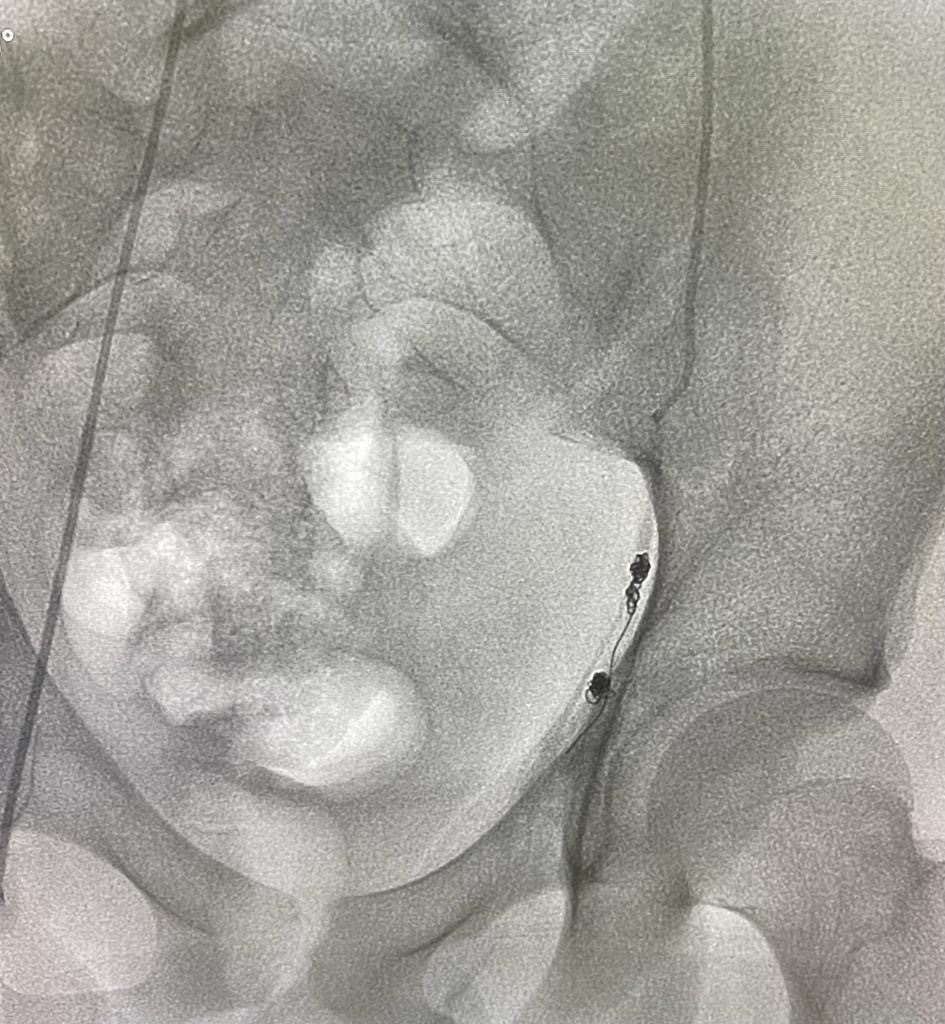

A varicocele is an enlargement of the veins within the loose bag of skin that holds your testicles (scrotum). It’s similar to a varicose vein you might see on your leg. Varicoceles are a common cause of low sperm production and decreased sperm quality, which can cause infertility.